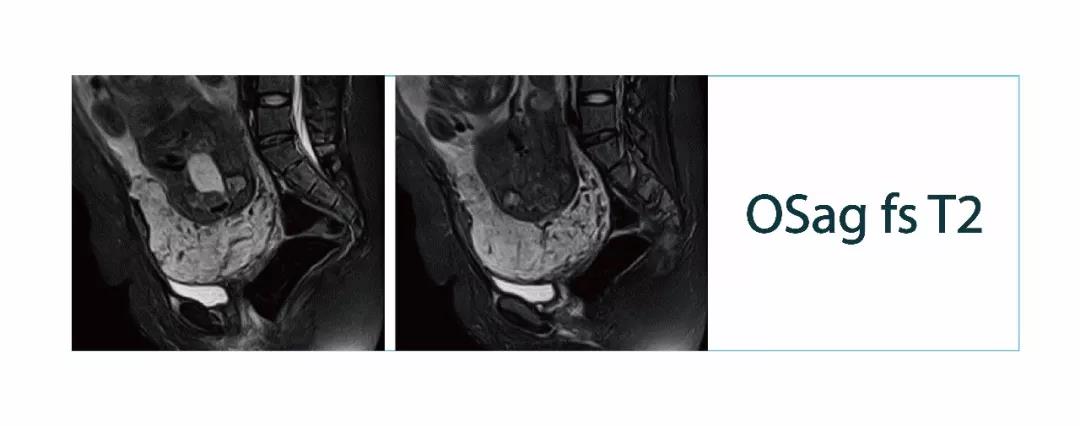

【朗润影像档案】20180323磁共振影像病例结果讨论

【朗润影像档案】磁共振影像病例分享(编号20180323)